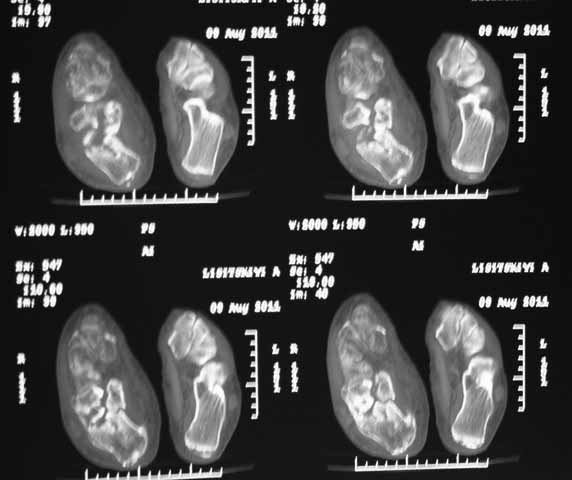

КТ перелома пяточной кости

Пациент 60 лет с производственной травмой-закрытые переломы правой пяточной кости,

тибиального плато слева поступил в феврале с.г. На 4 сутки выполнена открытая репозиция,

остеосинтез внутрисуставного перелома голени, ручная репозиция пяточной кости. Через три

месяца начал ходить с нагрузкой на обе ноги. Консолидация голени с полным восстановлением

функции колена. Правая стопа умеренно отечна, продольно распластана, длительная ходьба

вызывает боли и увеличение отека. Прошел несколько курсов ударно-волновой терапии,

грязелечение, боли и отек уменьшились. В наших планах -оформление на ВТЭК, через год

возможно выполнение подтаранного артродеза.Но после производства КТ в августе появились

сомнения в консолидации перелома.Ранее у нас не было опыта КТ переломов стопы и сканы привели

в замешательство.Прилагаю снимки со дня поступления, августовские пациентом не

представлены.С благодарностью примем советы коллег.